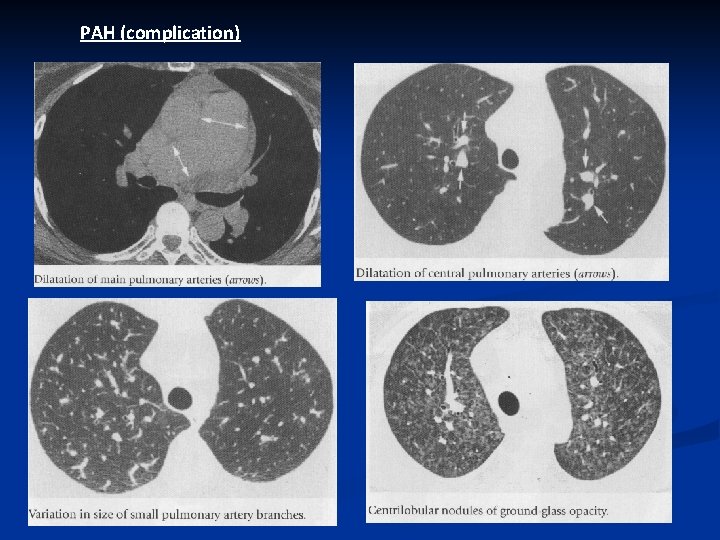

PAH (complication)